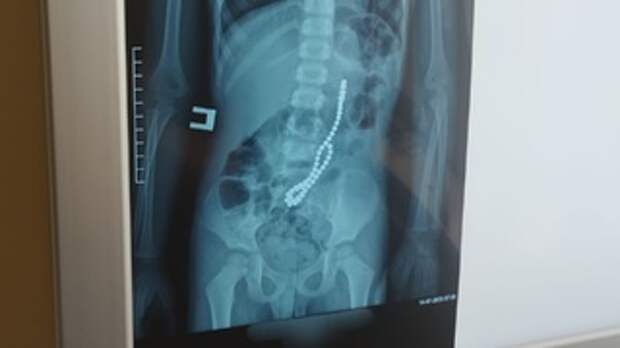

Новосибирские врачи удалили у 59-летнего жителя Алтайского края гигантскую опухоль. Она весила четыре килограмма и заполоняла всю грудную клетку, сдавливала легкие, пищевод, диафрагму и сердце. Об этом сообщили в Telegram-канале медучреждения.

Но в 2025 году пациент стал жаловаться на сердце. В груди возникли давящие боли, нарушился сердечный ритм, появилась одышка и осиплость голоса. Тогда алтайские онкологи обнаружили, что новообразование достигло гигантских размеров – до 45 см в поперечнике. Оно заняло всю грудную клетку, сместило и сдавило легкие, пищевод, трахею, диафрагму и сердце. Опухоль могла прорасти в сердце, поэтому пациенту рекомендовали обратиться за помощью в Центр Мешалкина.

Как рассказал ведущий торакальный хирург-онколог Центра Алексей Петров, у этой доброкачественной опухоли был злокачественный потенциал. Метастазов у пациента не было, но под ее давлением одно из легких не работало. Кроме того, нарушилась работа сердца – оно могло остановиться в любой момент.

Опухоль весила 4 кг, поэтому технически вмешательство было очень сложным. Чтобы полностью выделить ее, врачам пришлось выполнить два хирургических доступа. Кроме того, пациенту перелили около пяти литров крови.